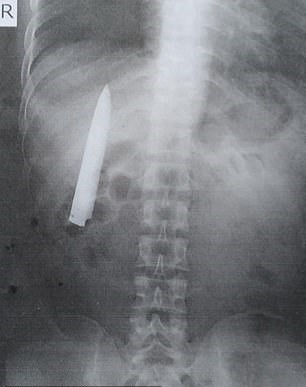

A 25-year-old man who was attacked by gang members more than a year ago was shocked to discover that he still had a knife buried in his torso.

He was rushed to a public hospital but the doctor who treated him only stitched his wound. It was not until he underwent an X-ray for a new job that he discovered the knife inside his torso.

The 25-year-old was shocked to learn that the blade of the knife was still in his body and very close to his lungs.